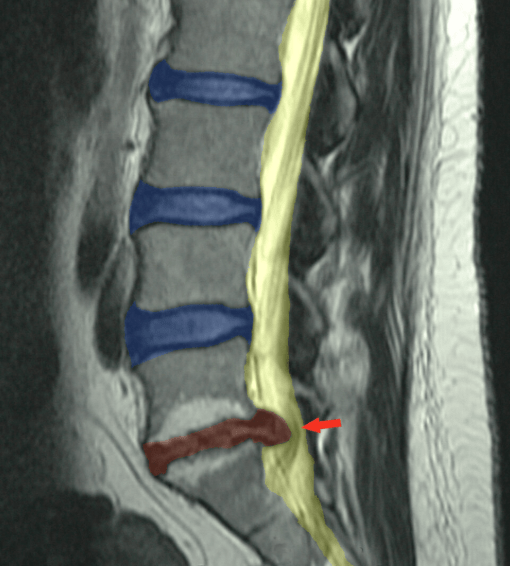

- Herniated Discs: A herniated disc happens when the soft part in the middle of a spinal disc pushes out through a tear in the outer layer. This may press on nerves close by and cause a lot of back pain.

- Bulging Discs: A bulging disc is when the disc sticks out because there is pressure, but the outer edge is not broken. It can still bring a strong pain in your lower back.

- Sciatica: Sciatica is pain that moves along the sciatic nerve. This nerve goes from your lower back, through the hips, and down each leg. A herniated disc or bone spur can press on the nerve, and that can cause discomfort.

The negative intradiscal pressure works kind of like a small vacuum. It helps pull the herniated or bulging disc back to where it needs to be. This takes the pressure off the nerves that get pinched. If nerves get pinched, you feel back discomfort or leg discomfort. By making this pressure lower, VAX-D can help with the cause of your symptoms.

This vacuum effect helps to pull the bulging or herniated disc stuff back inside the disc walls. That takes pressure off the spinal nerve roots near the disc. When this happens, it can stop the pain, numbness, or weakness that people feel. With no compression, VAX-D lets the nerve roots work the way they should.